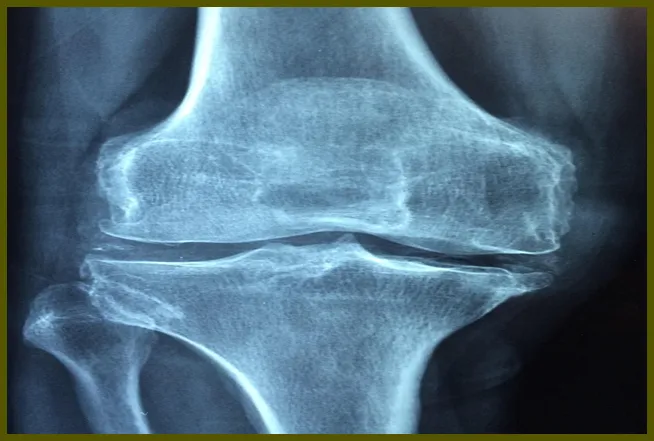

관절염은 무릎 통증을 유발하는 또 다른 주요 원인입니다. 노화나 반복적인 사용으로 인해 관절에 염증이 생길 수 있으며, 이는 무릎의 통증과 부종을 유발합니다. 특히 퇴행성 관절염의 경우 관절 연골이 마모되면서 통증이 증가할 수 있습니다.